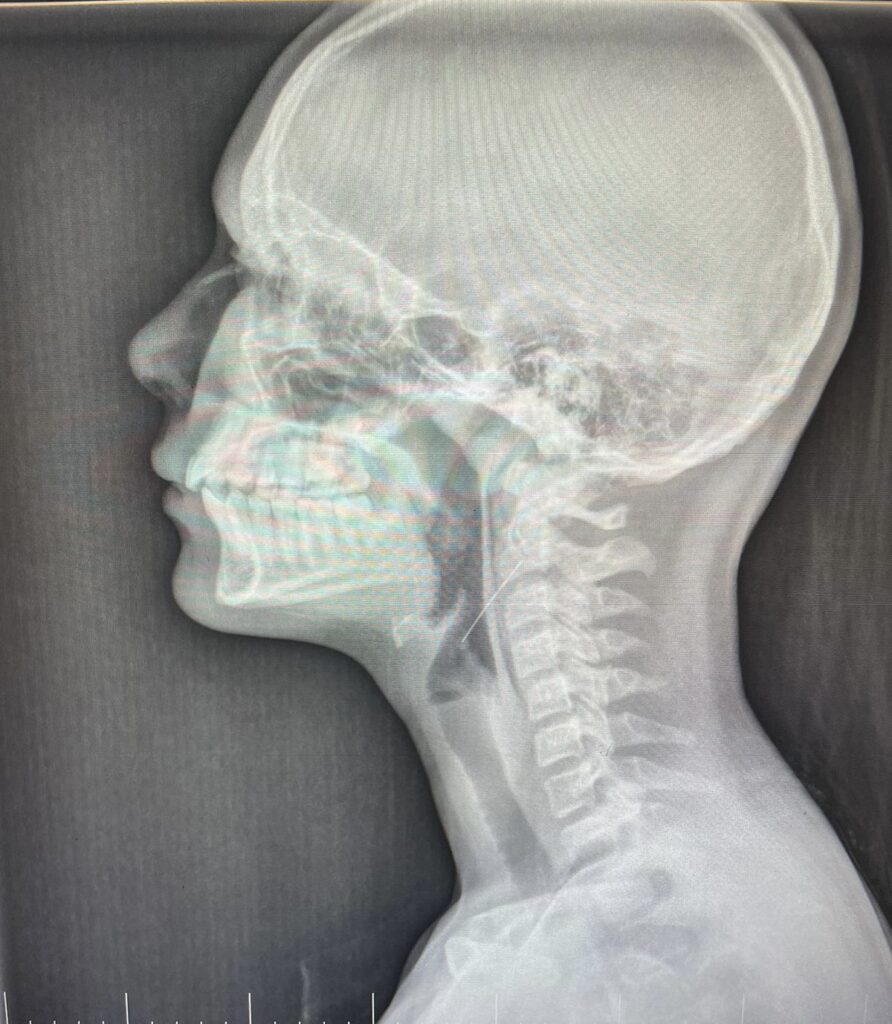

В процессе украшения дома гирляндой 13-летняя девочка держала иголку в зубах и при движении проглотила, после чего сразу почувствовала невыносимую боль и тошноту.

Операция длилась всю ночь. Хирургической бригадой во главе с заведующим оториноларингологического отделения А.И. Мащенко была проведена прямая ларингоскопия: обнаружено инородное тело — иголка, проникающая в правую стенку глотки и стоящая диагонально, тупым концом книзу и под эндоскопическим наблюдением иголка была удалена из горла.